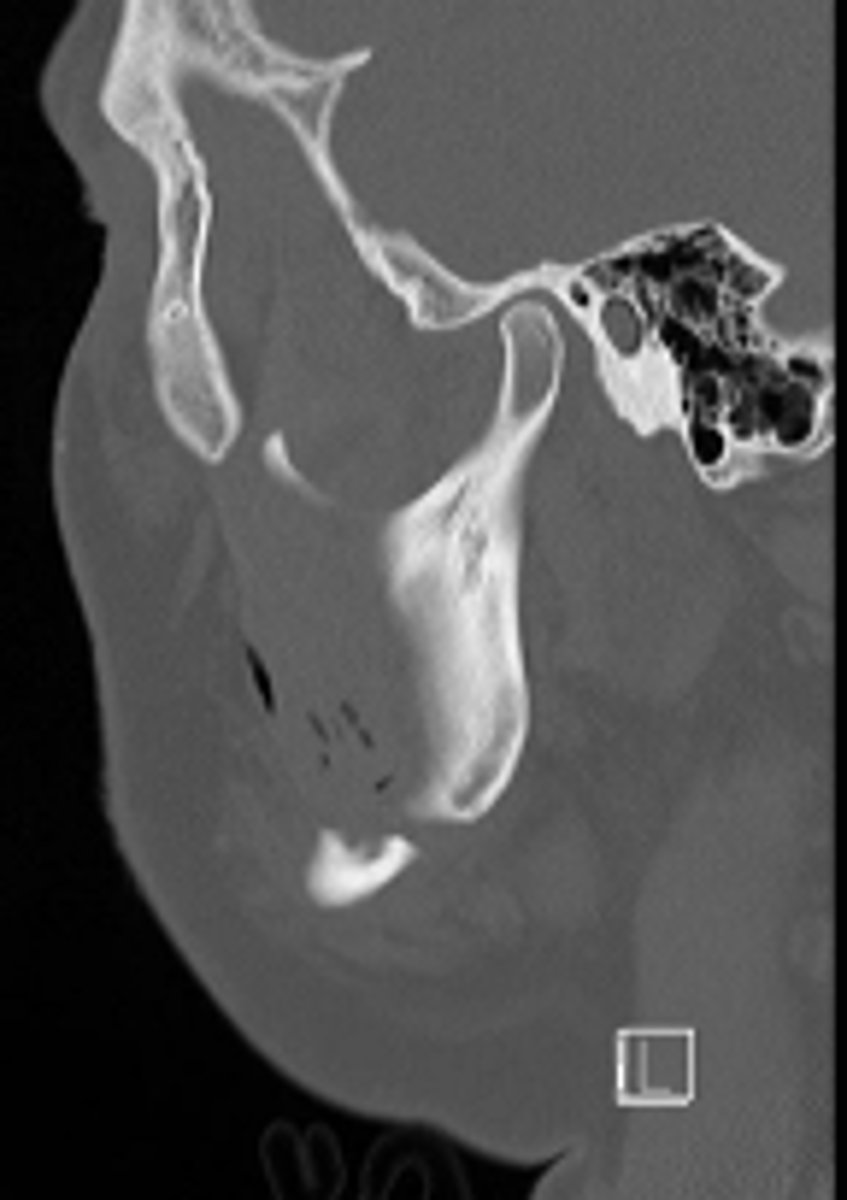

sagittal plane

ID the CT view: